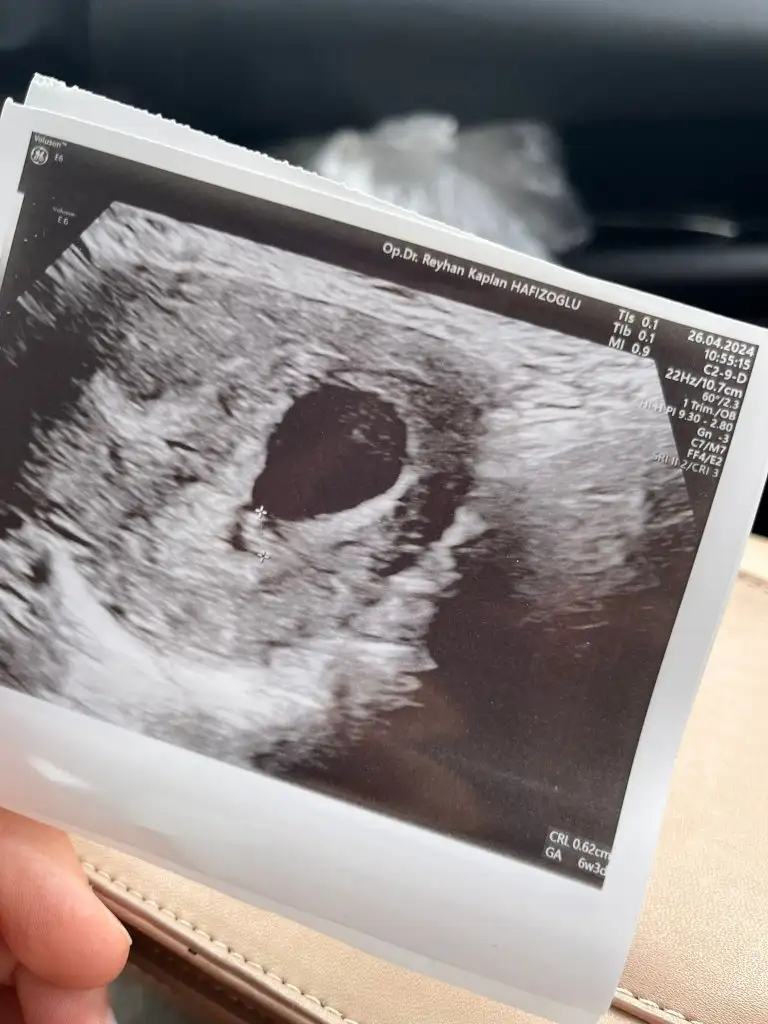

Ramziye göre erkekMerhaba benim içinde tahminde bulunabilir misiniz acaba6+1 karından ultrasonEki Görüntüle 3419437